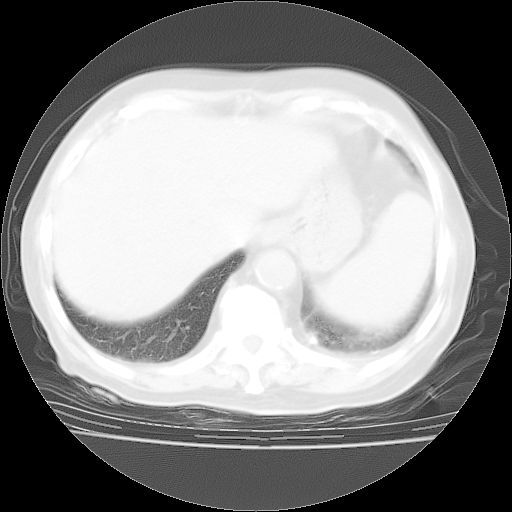

4月28日肺部CT——再次出现类似去年5月9日——透光度降低,“间质性”改变。

4月28日肺部CT——再次出现类似去年5月9日——磨玻璃样、间有“粟粒样”改变。